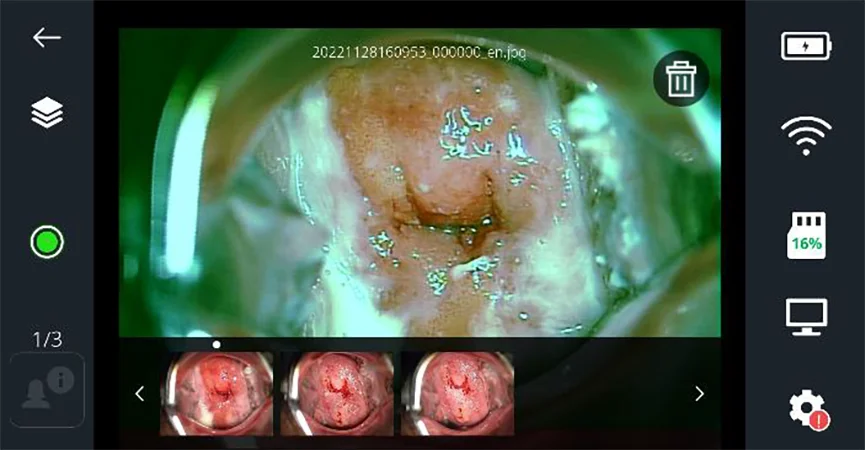

[НОГООН ФИЛЬТР]

• Ногоон фильтр асаалттай байхад зураг авч дараа нь хиймэл оюун ухааны үнэлгээнд илгээж болно.

• Ногоон фильтрийг унтрааж авсан зургийг товчийг дарснаар ногоон фильтр хийж болно.

Зураг 15 - Ногоон фильтр ажиллуулсан үеийн дэлгэцийн харагдах байдал

Тайлбар: Хэрэв ногоон фильтр асаалттай дүрс бичлэг хийсэн бол ногоон фильтрээр шүүсэн дүрс бичлэгийг тоглуулах болно. Хэрэв ногоон фильтрийг асааж дүрс бичлэг хийгээгүй бол хадгалсан дүрс бичлэгэн дээр дахин ногоон фильтрийг ашиглах боломжгүй.